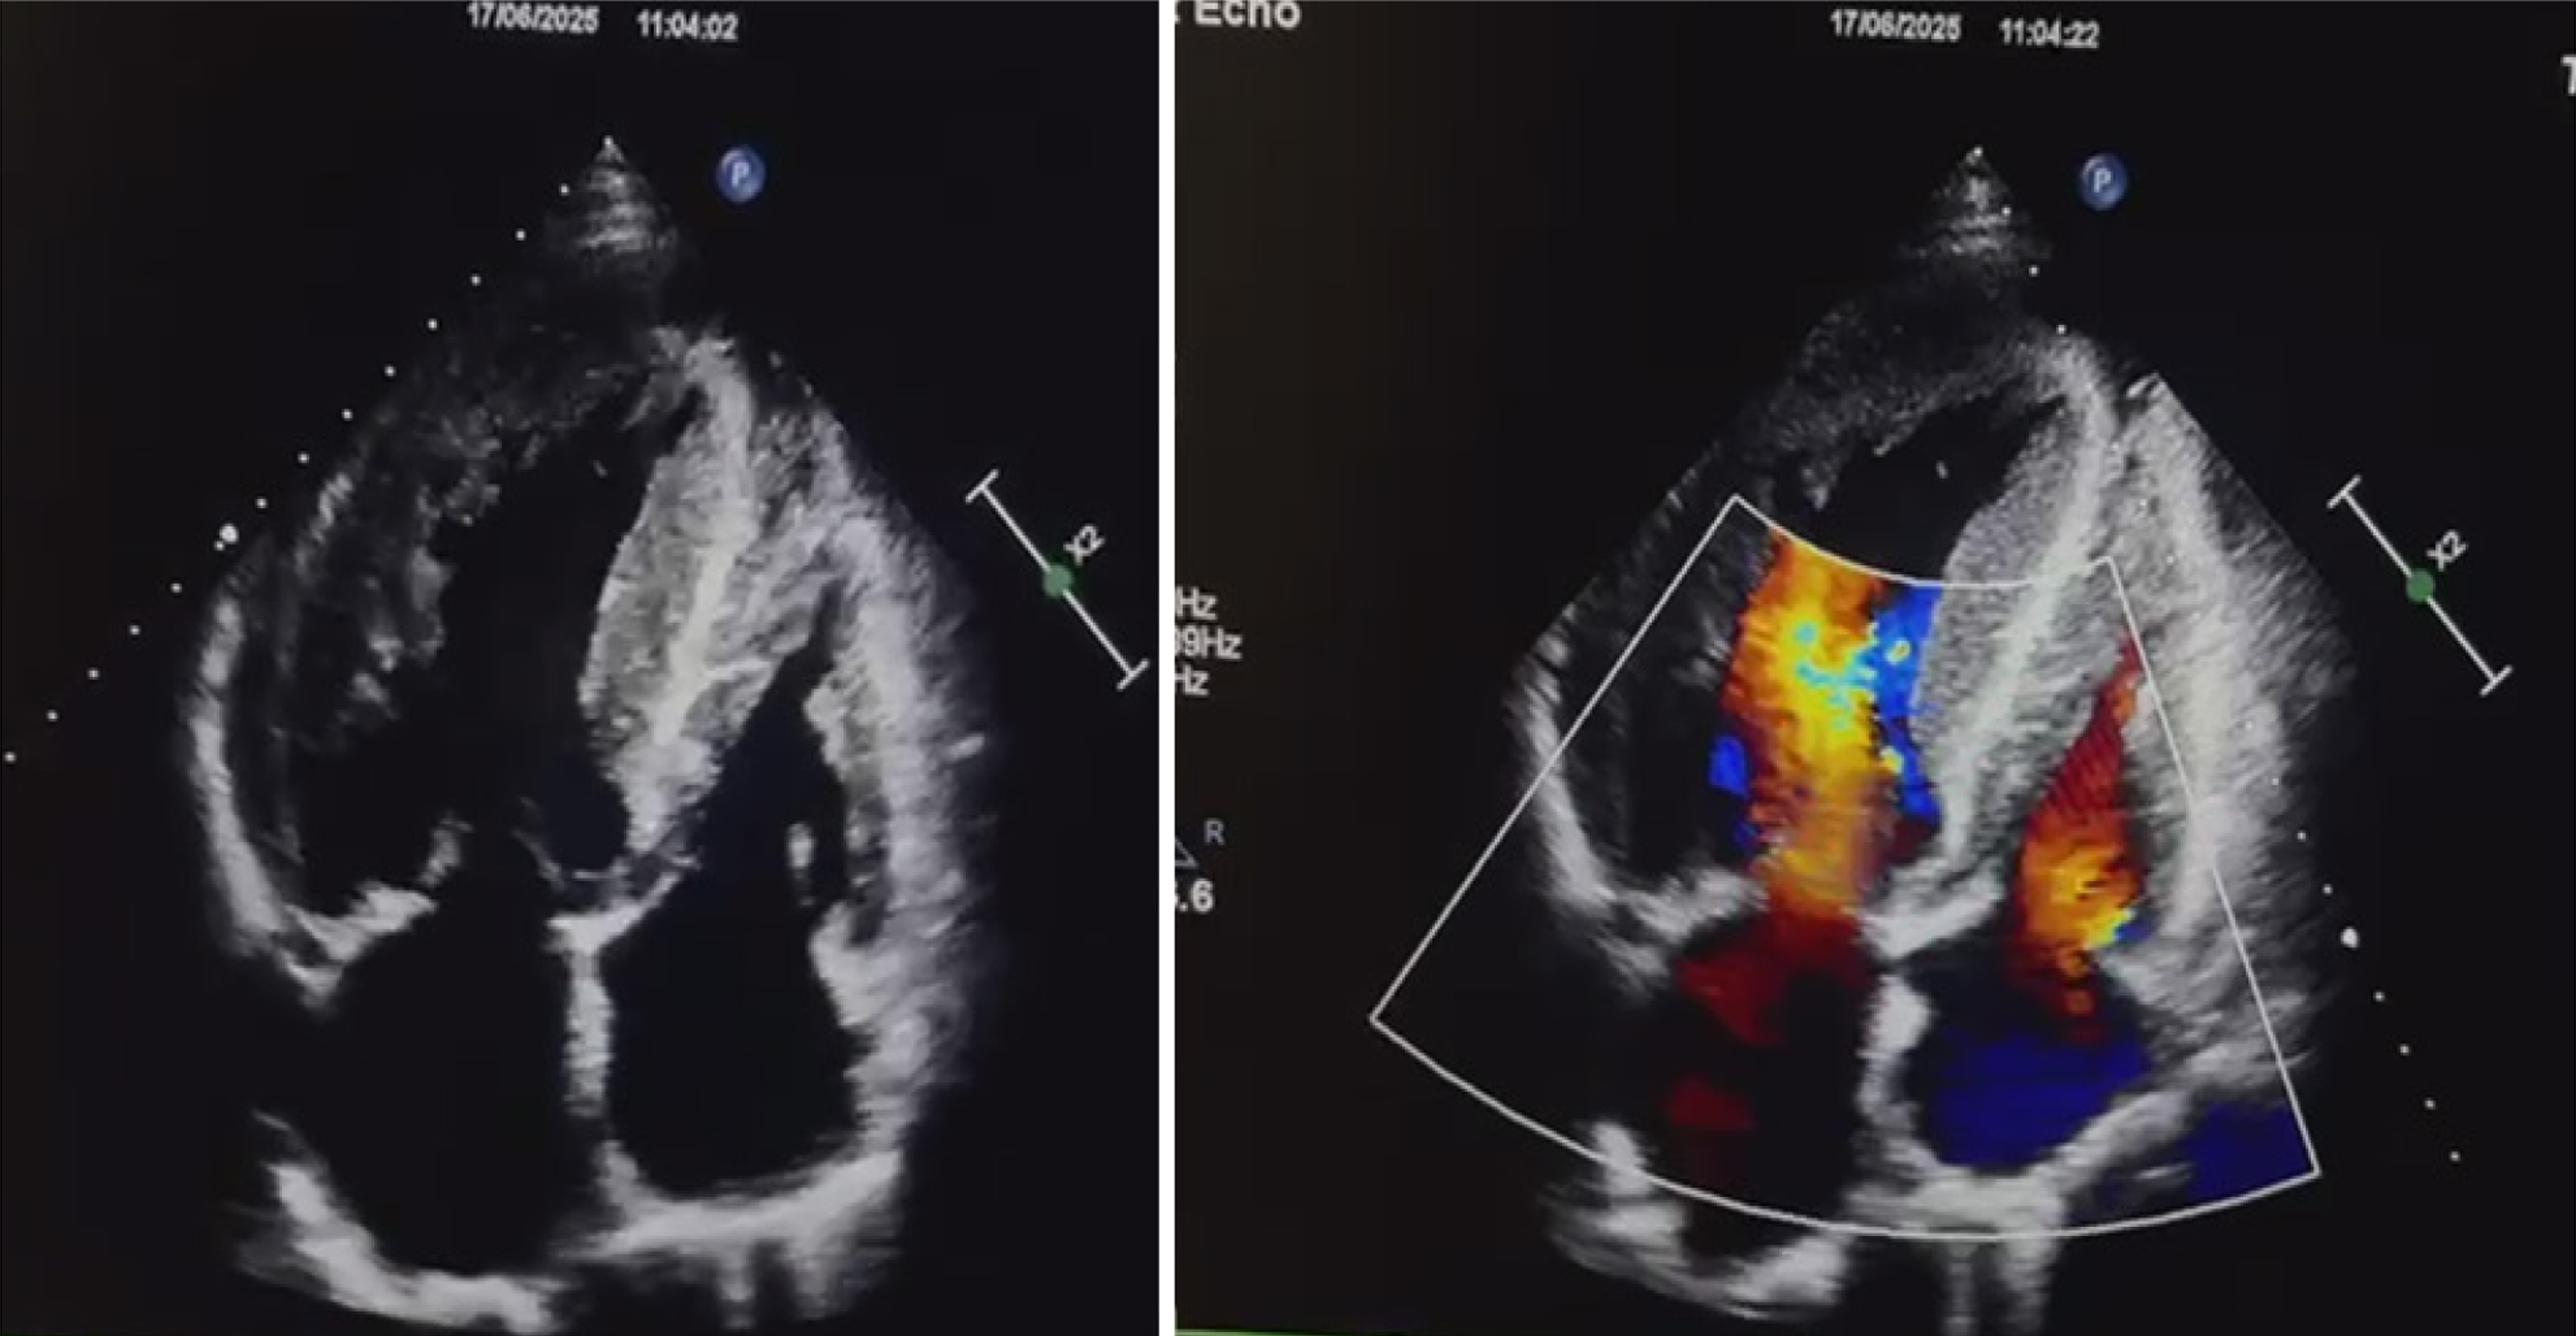

Figure 1 Transthoracic echocardiography showing asymmetric septal hypertrophy and dynamic left ventricular outflow tract obstruction with a resting gradient of 90 mmHg and 130 mmHg on Valsalva maneuver.